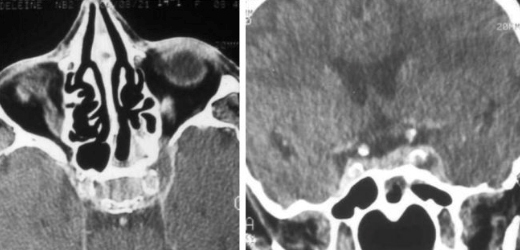

Un scanner cérébral injecté, à défaut d’une imagerie par résonance magnétique (IRM) injectée, est réalisé en urgence.

Question 8 - Interprétez-le :

Commentaire : On voit en effet l’hypodensité dans le sinus caverneux gauche qui correspond à l’absence de flux. Cheminent dans le sinus caverneux le nerf oculomoteur III, le nerf trochléaire IV, et les deux branches du nerf trijumeau V (1-2). C’est bien la carotide interne et non la carotide commune qui la traverse. Une des complications classiques d’une sphénoïdite aiguë est la thrombose du sinus caverneux. La thrombose intracarotidienne a contrario n’en est pas une complication classique ; la paroi artérielle carotidienne est, de par son épaisseur et solidité, un bon rempart à la dissémination intraluminale. En ce qui concerne les complications oculomotrices, seul le nerf abducens est susceptible d’être atteint dans une sphénoïdite aiguë mais l’atteinte des autres nerfs extracaverneux reste exceptionnelle.